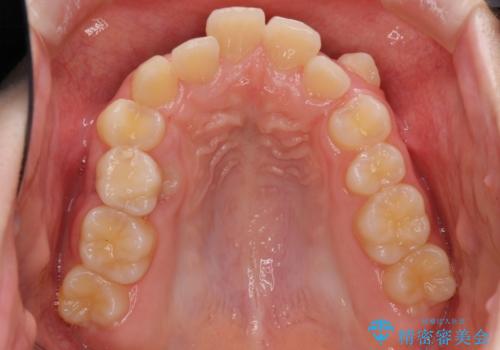

- 八重歯と乳歯が残っていることを気にして来院された患者様です。

乳歯が3歯残っており、下顎は左右ともに後続永久歯がない状態でした。

口元が突出しており、口が閉じにくかったため、乳歯を含め上下5歯を抜歯して矯正治療を行うこととしました。